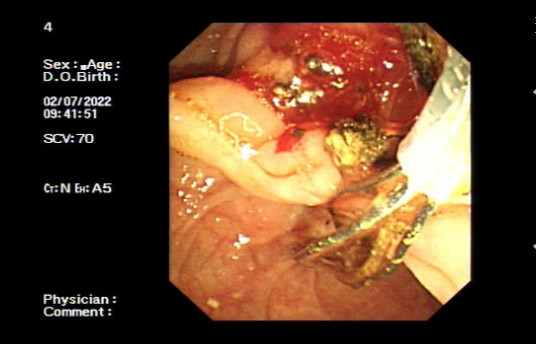

突如其来的腹痛、发热、寒战、黄疸近日,78岁的潘大爷讲述自己前些天毫无征兆突发腹部胀痛,伴有发烧、寒颤、恶心呕吐、胸闷、小便黄,实在忍不住,便...